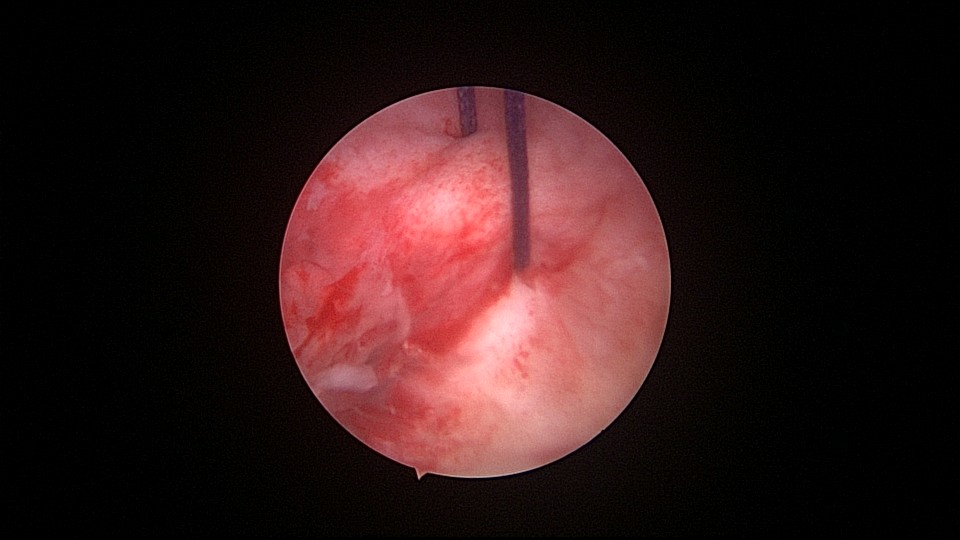

患者56岁,G4P1,顺产1次。1990、1991、1992年三次安环,均自然脱落,1993年第4次安环至今,共31年。现绝经4年,外院取环失败。患者阴道、宫颈、子宫萎缩,宫颈外口无法夹持,探针、中弯钳均无法打开宫颈外口,一筹莫展多时。最后用缝线缝住宫颈11点位及1点位,牵拉宫颈,尖刀片十字切开宫颈外口,B超监护下宫腔镜艰难进入宫颈管,见宫颈管封闭粘连,宫颈内口左侧粘膜下肌瘤遮挡视野。多次努力,镜子成功进入宫腔,见O型环两侧与子宫肌壁嵌顿,异物钳牵拉几次失败,用取环钩钩取,多次尝试终于成功钩住环,牵拉到宫颈外口,用中弯钳取出节育环,环变形,宫壁见节育环割裂痕迹,宫腔少许积血,无其他异常。